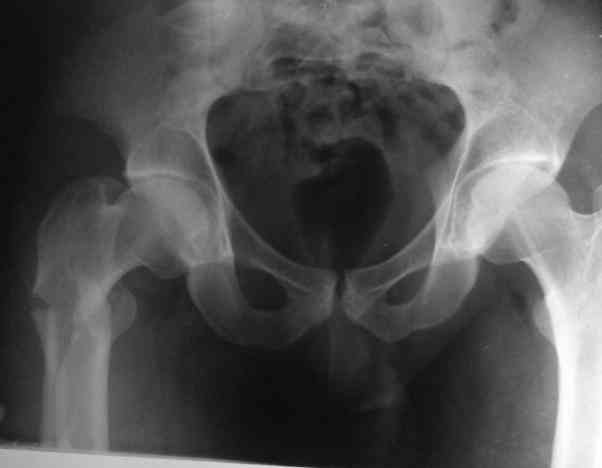

Male, 75 yrs old.

Right hip fracture as an interthrocanteric with extension to diaphysis Tronzo V.